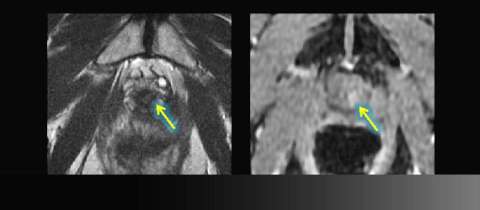

LEFT: Axial T2-weighted image: slight asymmetry at the vesicourethral anastomosis could be post-surgical change

RIGHT: Corresponding asymmetric enhancement raises suspicion for focal recurrence